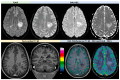

Primary Angiitis of the Central Nervous System (PACNS) is a rare disease and its diagnosis is a challenge for several reasons, including the lack of specificity of the main findings highlighted in the current diagnostic criteria. Among the neuroimaging pattern of PACNS, a tumefactive form (t-PACNS) is a rare subtype and its differential diagnosis mainly relies on neuroimaging. Tumor-like mass lesions in the brain are a heterogeneous category including tumors (in particular, primary brain tumors such as glial tumors and lymphoma), inflammatory (e.g., t-PACNS, tumefactive demyelinating lesions, and neurosarcoidosis), and infectious diseases (e.g., neurotoxoplasmosis). In this review, the main features of t-PACNS are addressed and the main differential diagnoses from a neuroimaging perspective (mainly Magnetic Resonance Imaging-MRI-techniques) are described, including conventional and advanced MRI.